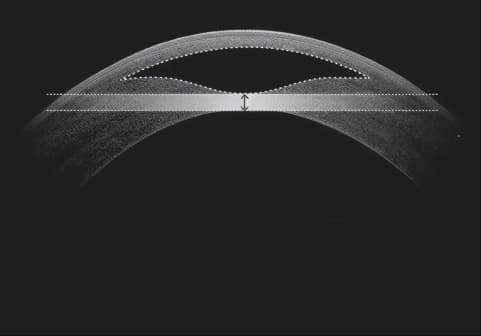

렌티큘 사이드컷 디자인 특허

각막 내부에 만들어진 렌티큘을 안구의 다른 부분 손상 없이 제거하기 위해 만드는 수직·사이드 절개면으로

렌티큘 추출 과정에서 안전성을 높여, 렌티큘 손상(찢김) 방지하고

건조함이나 통증을 줄일 수 있도록 설계된 자이스의 특허기술 입니다.

렌티큘이 제대로 제거되지 않을 경우

부정 난시등을 유발

1 1 사이드컷

2 2 Min thickness (최소 렌티큘두께)

렌티큘 추출 과정에서의 기술특허 정확한 수술을 위한 비쥬맥스만의 안전장치

출처 : Variation of Lenticule Tickness for SMILE in Low Myopia- Siedlecki, JRS, 2018